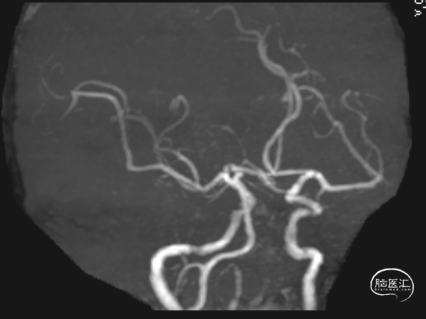

术后第3天患者恶心、呕吐症状消失,仍有头晕,复查DWI及MRA。

术后第5天,头晕症状完全消失,双上肢收缩压差8mmHg,NIHSS 0分。